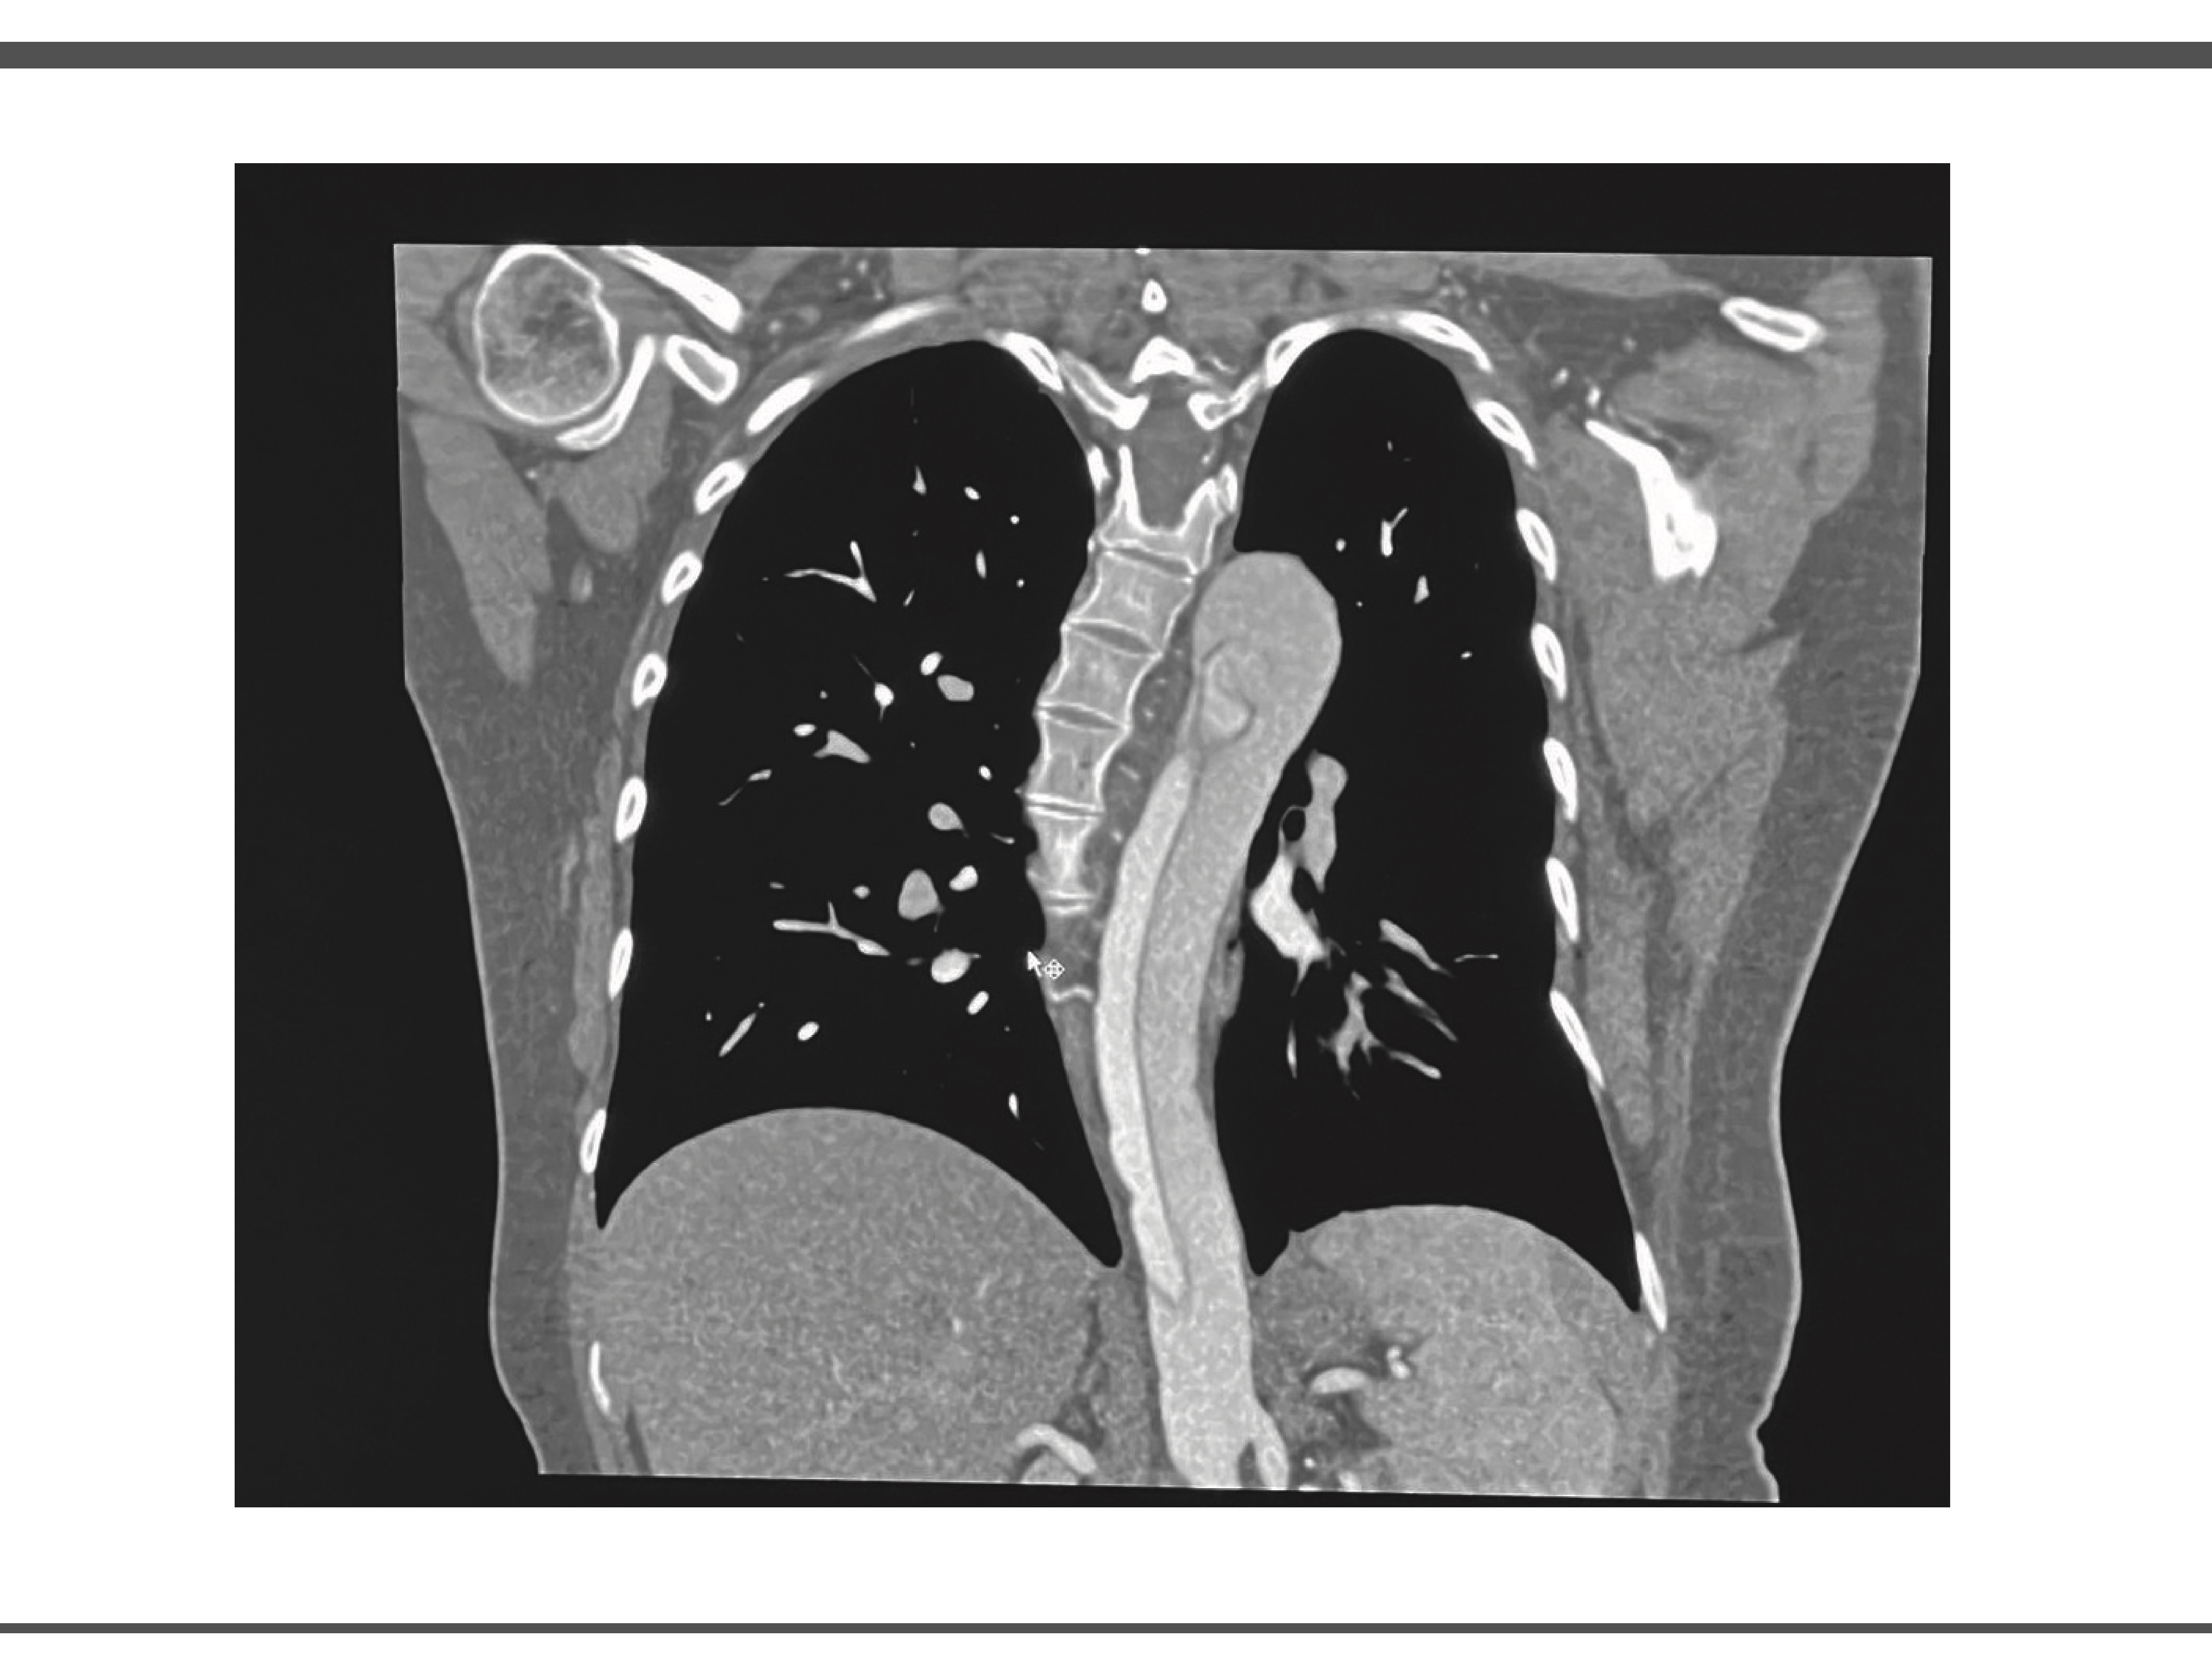

Durante su estancia en UCI se realiza angiotomografia en donde se obtienen imágenes compatibles con disección aortica, así como valoración por el servicio de angiología y cirugía vascular en donde se observó arco aórtico tipo II, con disección inmediatamente posterior a ostium de arteria subclavia izquierda, con extensión observable en ultimo corte en la aorta infrarenal con ramas viscerales dependientes de luz verdadera, por lo que la paciente es candidata a exclusión endovascular de segmento torácico y viscerales, pero debido a ausencia de insumos endovasculares y capacidad resolutiva, no es posible realizar este procedimiento en nuestro hospital. (Ilustración 2 y 3)

IMAGEN 2.

Fuente: Expediente de paciente. Fecha Marzo 2025